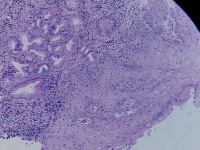

贲门活检

性别

男

年龄

68岁

上腹部不适,贲门可见不规则病灶,触之易出血

贲门粘膜

大体所见

腺癌